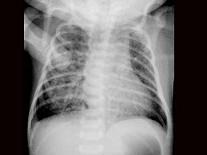

问题 患儿,男,1天,生后呼吸困难,羊水见胎粪污染,如图,最可能的诊断为?(?)

选项 A.新生儿肺炎 B.新生儿湿肺 C.新生儿肺出血 D.新生儿呼吸窘迫综合症 E.胎粪吸入综合征

答案 E